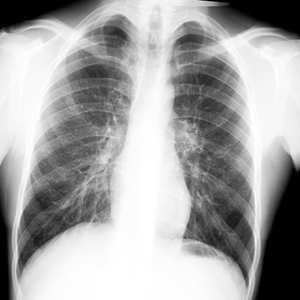

Для того, чтобы не допустить развития запущенных форм туберкулеза, в нашей стране все взрослые и подростки 15 лет и старше 1 раз в 2 года обязательно проходят флюорографию или рентгенологическое обследование легких.

Профилактикой туберкулеза во взрослом возрасте является ежегодное диспансерное наблюдение и выявление заболевания на ранних стадиях. С целью выявления туберкулёза на ранних стадиях взрослым необходимо проходить флюорографическое обследование в поликлинике не реже 1 раза в год (в зависимости от профессии, состояния здоровья и принадлежности к различным группам риска). Чтобы избежать этого коварного заболевания, следует повысить сопротивляемость организма, вести здоровый образ жизни, который включает рациональное питание, отказ от вредных привычек, занятие физкультурой, спортом, закаливание своего организма.

Туберкулез – инфекционное заболевание, вызываемое различными видами микобактерий – Mycobacterium tuberculosis (палочка Коха). Туберкулез обычно поражает легкие, реже затрагивает другие органы и системы (кости, суставы, мочеполовые органы, кожу, глаза, лимфатическую систему, нервную систему). При отсутствии лечения заболевание прогрессирует и заканчивается летально. Наряду с человеком, туберкулезом могут быть инфицированы и животные (крупный рогатый скот, грызуны, куры и др.).

При открытой форме туберкулеза в мокроте определяются микобактерии туберкулеза. Открытой формой считается форма туберкулеза, при которой имеется очаг поражения (распад в легком, язвенная форма туберкулеза в бронхах). При такой форме больной считается заразным для окружающих.

При закрытой форме туберкулеза микобактерии в мокроте не обнаруживаются. Больные не предоставляют опасность для окружающих.